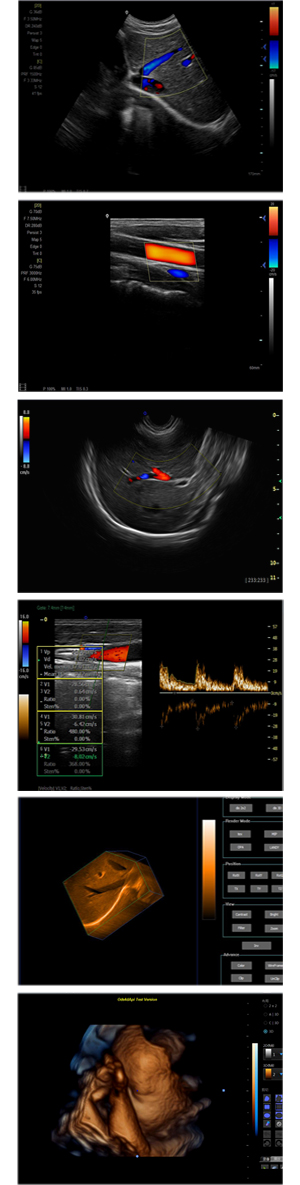

XF-7800型,秉承先鋒彩超技術(shù)之精華,擁有高雅大氣的獨特外型,為最新一代應(yīng)用型數(shù)字彩色多普勒診斷系統(tǒng),魅力與實力相融合??蓮V泛適用于腹部、婦產(chǎn)科、心臟、小器官、乳腺、肌骨及外周血管等諸多方面的診查,讓您在臨床超聲診斷應(yīng)用領(lǐng)域得心應(yīng)手,綻放異彩!

突破的成像技術(shù)

● 3D/ 4D成像技術(shù)/限7800選配

● 應(yīng)用于腹部、腎臟、泌尿系統(tǒng)、產(chǎn)科、婦科、盆腔、大動脈、肌肉組織、小器官、乳腺、心臟等

● 能量多普勒成像(PDI)

● 彩色血流量圖(CDE)

● 脈沖頻譜多普勒成像(PW)